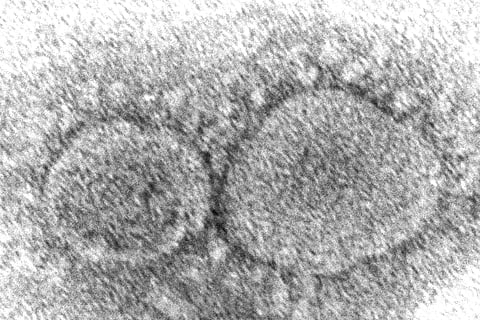

59 நாடுகளுக்கு பரவிய ஒமைக்ரான் கரோனா தொற்று

ஒமைக்ரான் வகை கரோனா வைரஸால் பாதிக்கப்பட்ட நாடுகளின் எண்ணிக்கை 59ஆக அதிகரித்துள்ளது.

உருமாறிய ஒமைக்ரான் கரோனா வைரஸ் பரவல் பல்வேறு நாடுகளில் கண்டறியப்பட்டு வருகிறது. தொற்று பரவலைக் கட்டுப்படுத்த தீவிரமான நடவடிக்கைகளை உலக நாடுகள் மேற்கொண்டு வருகின்றன.